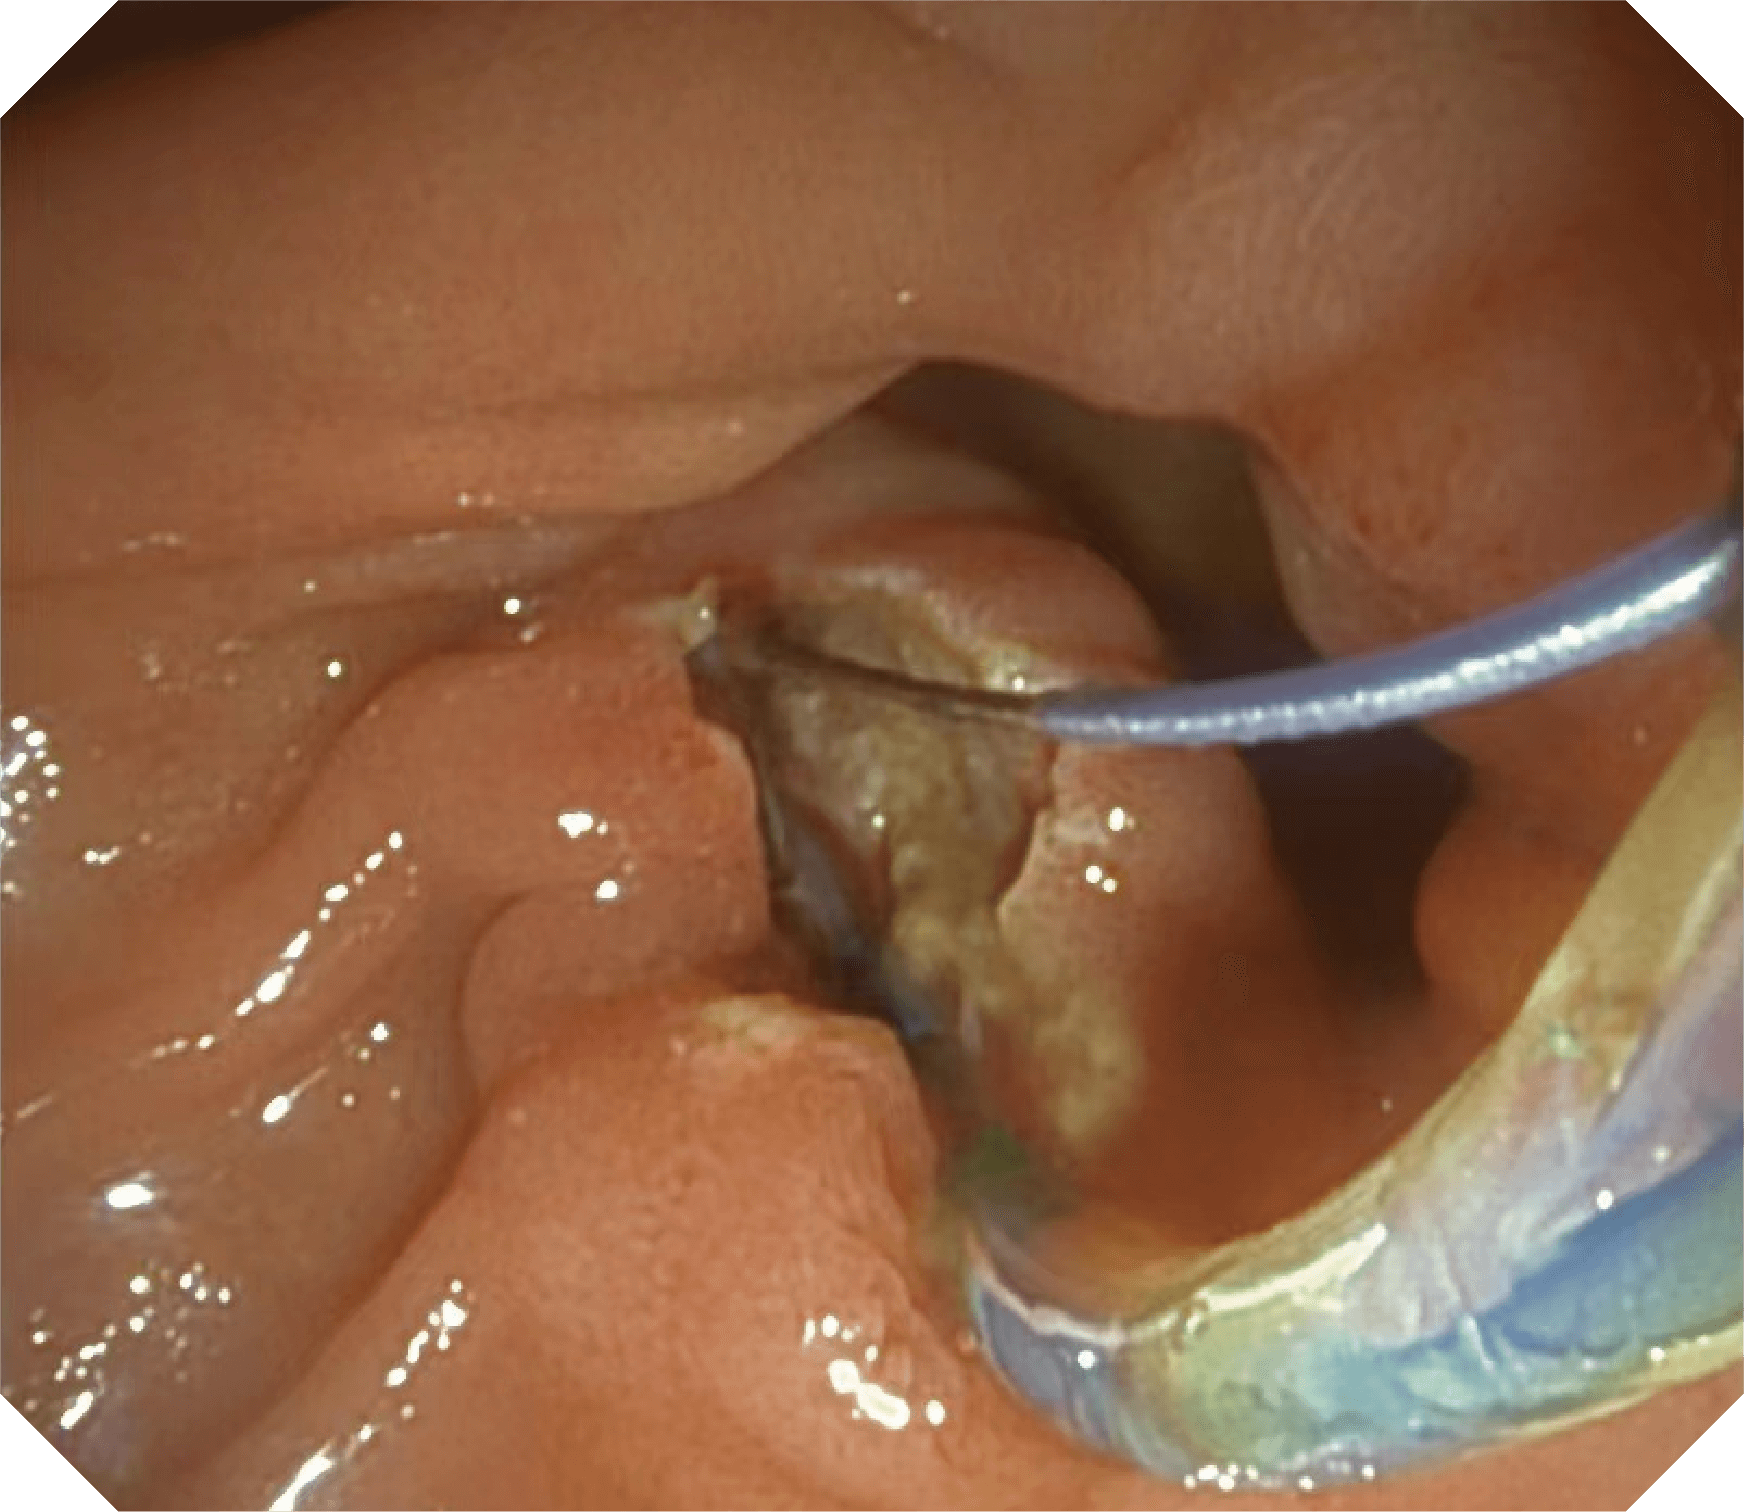

V槽设计提升导丝控制

优异的手术器械抬举性